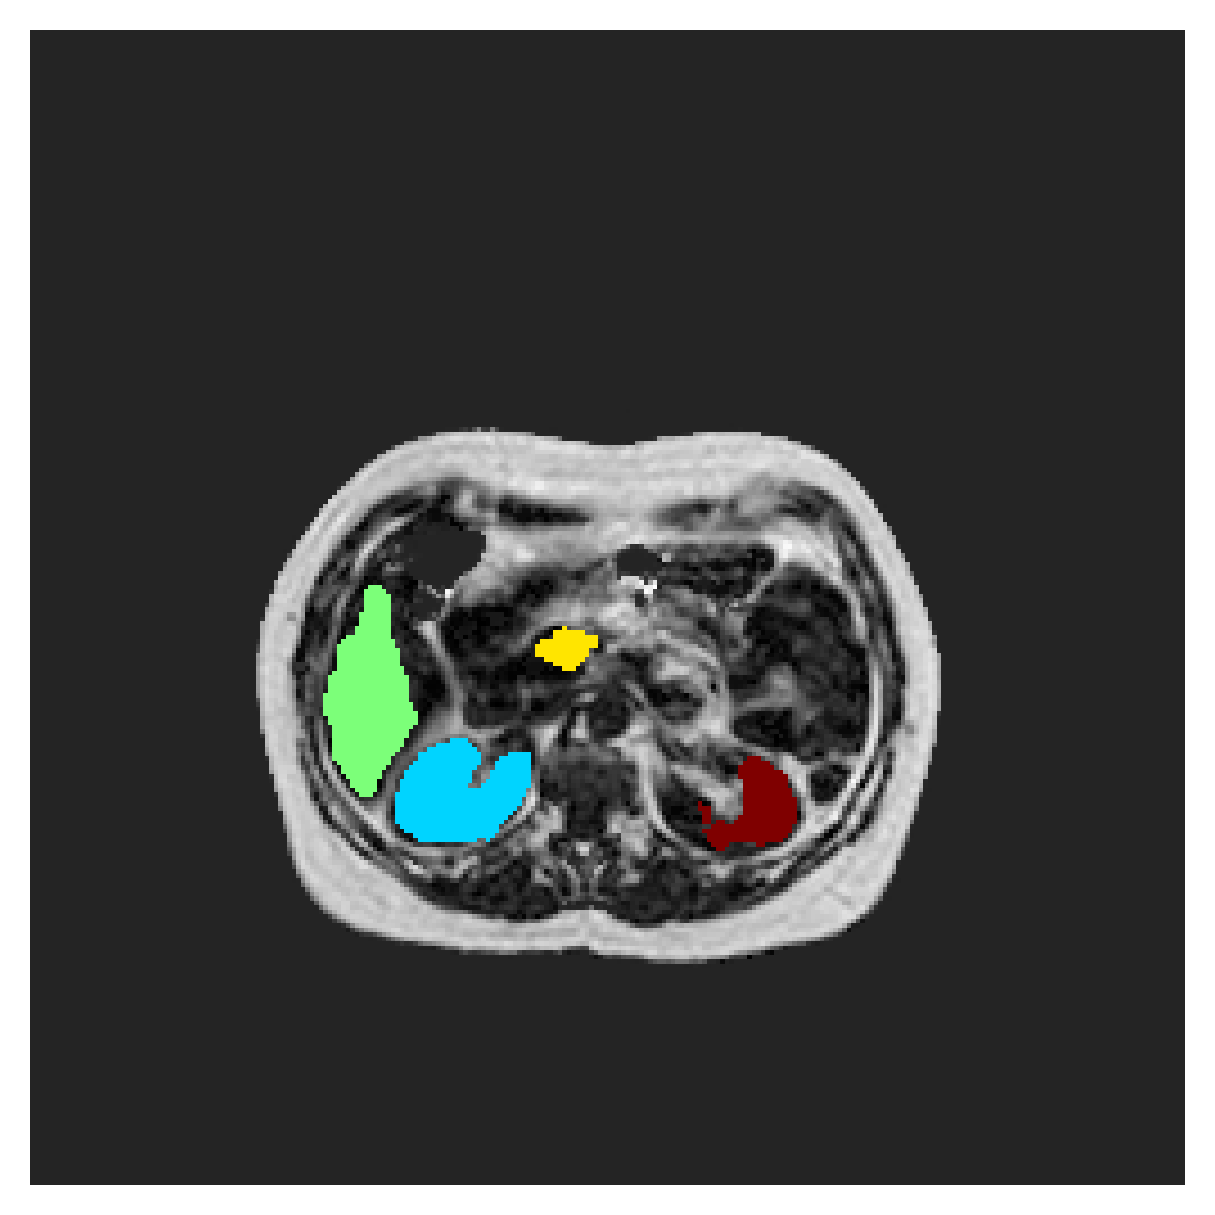

POEM

The Prospective investigation of Obesity, ENergy production and Metabolism (POEM) is a local (not currently publicly available; PI: L. Lind, see [22] for details) cohort of whole-body fat/water separated MR images. Full annotations of the liver, kidneys, bladder, pancreas and spleen are available for 50 subjects, providing a challenging segmentation dataset with heavily imbalanced classes of varying shapes. The resolution of the data is anisotropic, with reconstructed voxel size of in left-right, anterior-posterior and foot-head directions, respectively. For additional technical details regarding the acquisition and specifications of the images see [22].

The images contain two channels, one for water and one for fat content. For training, we normalize the volumes (per channel) and use 2D slices in the coronal plane, sized . The weak annotations are created synthetically, following the same procedure as described for the ACDC dataset.

5.2 Abdominal organ segmentation

Using 2D distance maps

In Table 3, the average DSC and HD95 results are shown (both using 2D and 3D distance maps) for the task of abdominal organ segmentation in POEM data (for boxplots see figures 8 and 9). We see that training with and (with distances calculated on 2D slices) performs comparably, while using and produces lower scores in both DSC and HD95 metric. On this dataset, the CRF-loss is able to compete with the boundary loss-based training strategies, even outperforming them on most classes. Most notably, all models trained with boundary loss appear to have a hard time segmenting the liver. We hypothesize this may be due to extremely severe class imbalance, as the liver covers a very large area compared to the rest of the classes. It is thus also more strongly affected by undersegmentations.

Using 3D distance maps

Inspecting the values of training with on distance maps computed in 3D from Table 3, we notice that the results generally improve over values achieved by using 2D distance maps. Most notable decreases are visible in HD95 values, as using volume-calculated distance maps provides more global information and additionally penalizes spatially unreasonable segmentations. The methods based on are now able to compete with the CRF-loss, in particular the one.

5.2.1 Qualitative comparison

In Figure 11 and 12 we show the same random slices in cases of calculating the boundary loss on 2D- and 3D-based distances, respectively. Comparing the two figures again indicates that the intensity-aware distances offer most improvement when calculated in 3D over 2D. The exception here is the MBD, which seems to even slightly degrade for most classes.